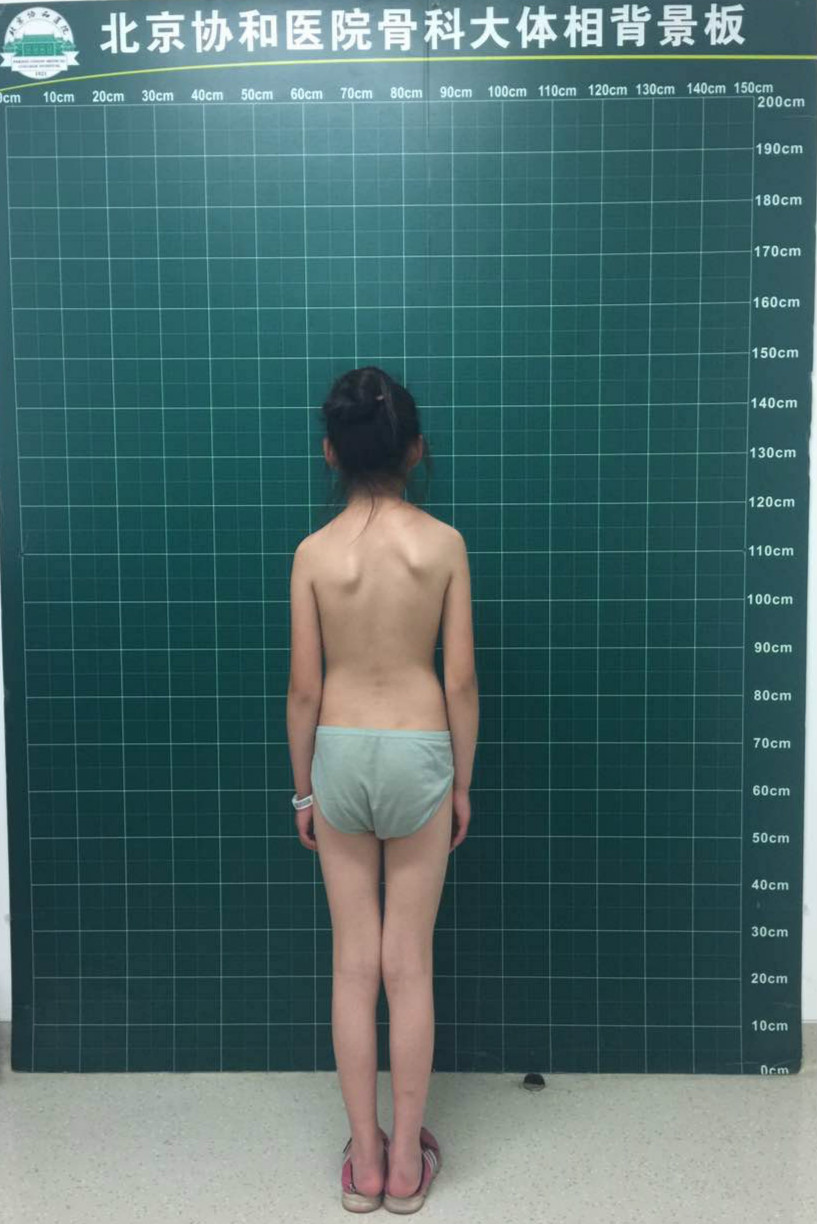

先天性脊柱侧凸站立位全脊柱正侧位:胸椎右侧弯,cobb角53°(t2-t7),t3

最近完成的一例特发性脊柱侧弯

12岁女孩脊柱侧弯曲超过60度,手术矫正后"长高"4厘米

12岁女孩脊柱侧弯,"惠人 大兴"联合实施全脊柱矫形术